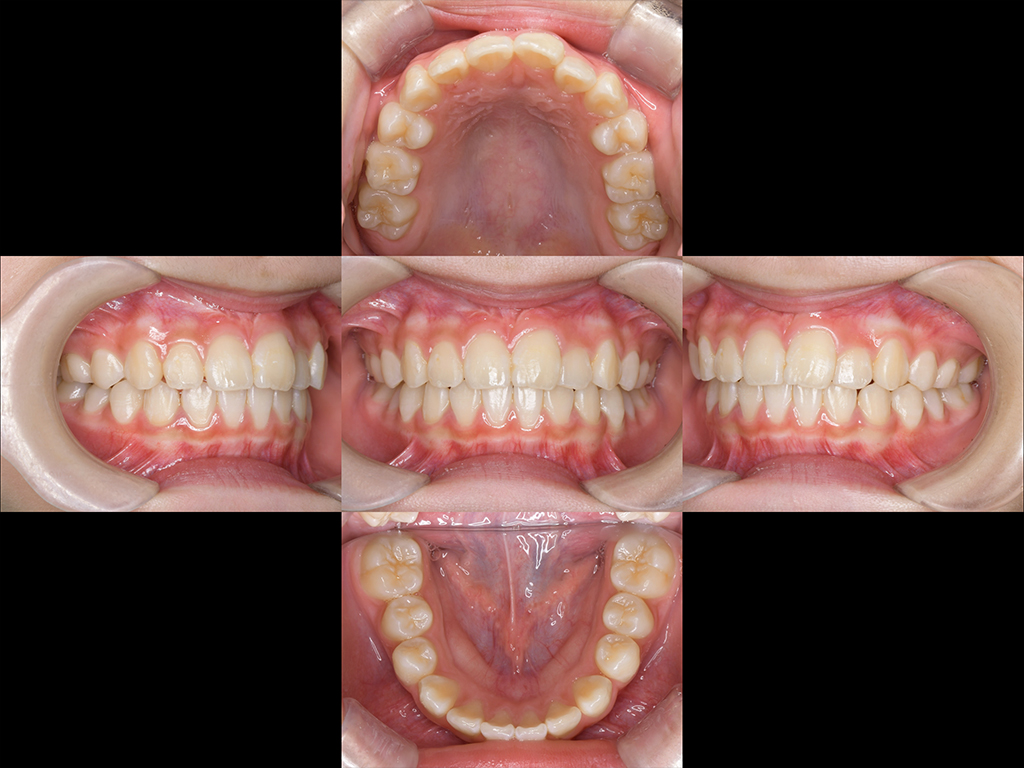

Before

After

| 年齢 | 13歳 女性 |

|---|---|

| 治療方法 | 矯正治療 インビザライン ホームホワイトニング |

| 治療期間 | 1年6ヶ月 |

| 治療費用 | 880,000円(税込) |